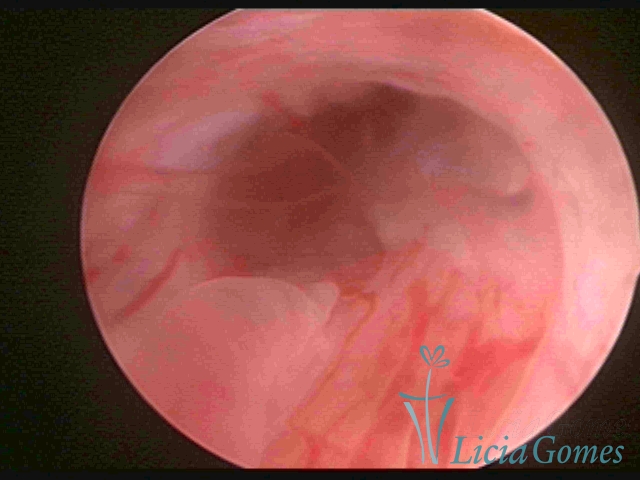

ENDOCERVICAL POLYPS

Benign tumors resulting from the reactive focal proliferation to inflammatory processes or hyperestrogenism situations, which may be sessile (with a large implantation) or stalked.